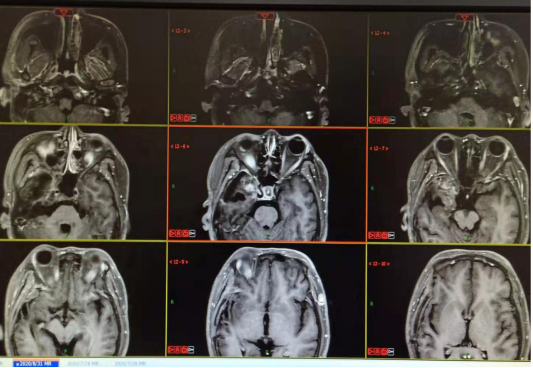

2021.01.08三门峡市中心医院:右侧颞叶胶质瘤术后改变,右额叶病灶较前增多,原脑干、右侧额叶病灶较前体积增大,考虑肿瘤进展。